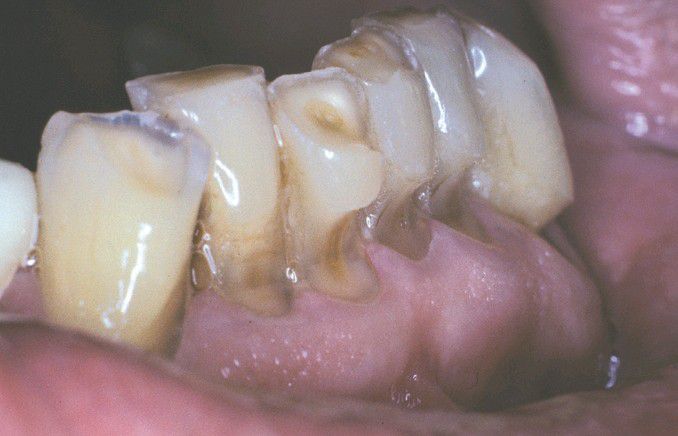

Abrasion

Horizontal cervical notches on the anterior mandibular dentition. Note visible pulp canals that have been filled with tertiary dentin.